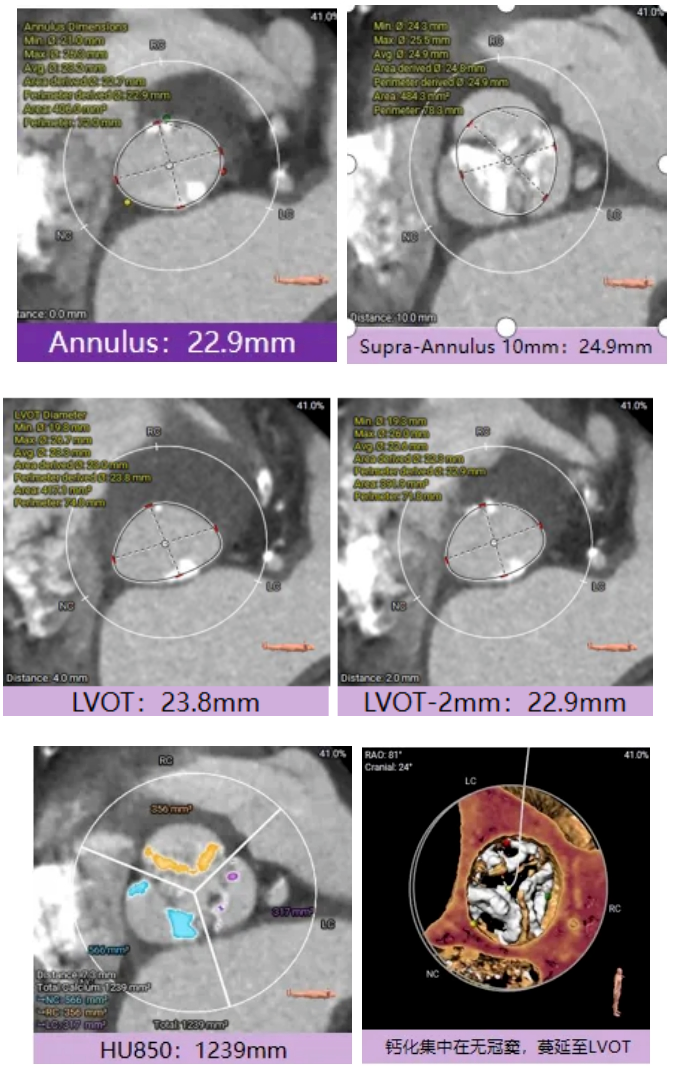

宋光远教授 首都医科大学附属北京安贞医院(点击查看专家详细简历) 技术革新不止,创新求索不辍:一切从患者出发,不断追求创新是内心的坚定。当年‘ALL IN ONE’的探索,正是怀揣着这份初心 —— 通过整合器械与操作,将入路创伤缩至最小,让患者在微创中更快康复,这是技术对患者的温柔承诺。而术中脑保护,是我们为安全筑牢的另一道防线。 此次预装干瓣的临床应用,让我们直面瓣膜“耐久性“临床困境,期待创新技术助力全生命周期管理! 病例概览 患者病史 患者因 “劳力性呼吸困难半年余,加重 20 天” 入院。高血压病史 20 年,最高血压 160/110mmHg;高脂血症病史;反流性食管炎。 超声提示:主动脉流速 Vmax 4.66 m/s,平均压差 53mmHg,左室射血分数(LVEF)40%; 超声诊断:主动脉瓣狭窄(重度)、主动脉瓣反流(轻中度)、二尖瓣狭窄(轻度)、二尖瓣反流(轻度)、三尖瓣反流(轻中度)、左房增大,左室肥厚。 术前CT 瓣环(Annulus)直径:22.9mm,左室流出道(LVOT)直径:周长径 23.8mm;总钙化负荷1239mm³(HU850),钙化集中于无冠窦,且蔓延至 LVOT,呈重度钙化表现;LVOT-Annulus 呈微直筒型,瓣上限制较重。左冠脉开口高度略低,瓣叶不长、窦部空间较大,结合钙化分部情况,预估双侧冠脉遮挡风险较低。室间隔膜部较短(2.4mm)有一定PPI风险,心室大小可,心脏角度64°,升主长度短于胶囊腔长度,同轴有一定困难。 · 造影角度及入路情况:主动脉弓角度可,但降主动脉折曲明显,双侧髂股动脉存在粥样硬化。 手术策略 采用 “极简式” 手术方案:18/20mm 球囊预扩张,植入金仕生物 Prostyle-A 预装干瓣(AV 26),配合长鞘,同时植入脑保护装置以降低卒中风险。 手术过程 球囊预扩:18号球囊预扩 输送系统顺利过弓跨瓣: 瓣膜植入:工作位观察位置适宜,完成植入。 术后即刻:术后造影显示瓣膜位置佳 入路与血管:撤出大鞘后检查,降主动脉仍存在较大弯折;入路闭合良好,无明显出血或血管并发症。 Prostyle A®预装干瓣——助力临床最优化解决方案: √ Mircro-EX™专利抗钙化技术:极简式预装干瓣,不使用戊二醛浸泡,减少钙化成因,干态存储的瓣膜术中无需清洗瓣膜,减少组装步骤,缩短手术时间,尤其适合复杂病例中的高效操作; √ 平衡的径向支撑力:重度钙化的患者,形态展开良好,在横位心等复杂情况下实现稳定锚定及释放; 专家简介 苑飞 首都医科大学附属北京安贞医院(点击查看专家详细简历) 姚晶 首都医科大学附属北京安贞医院(点击查看专家详细简历) · END ·